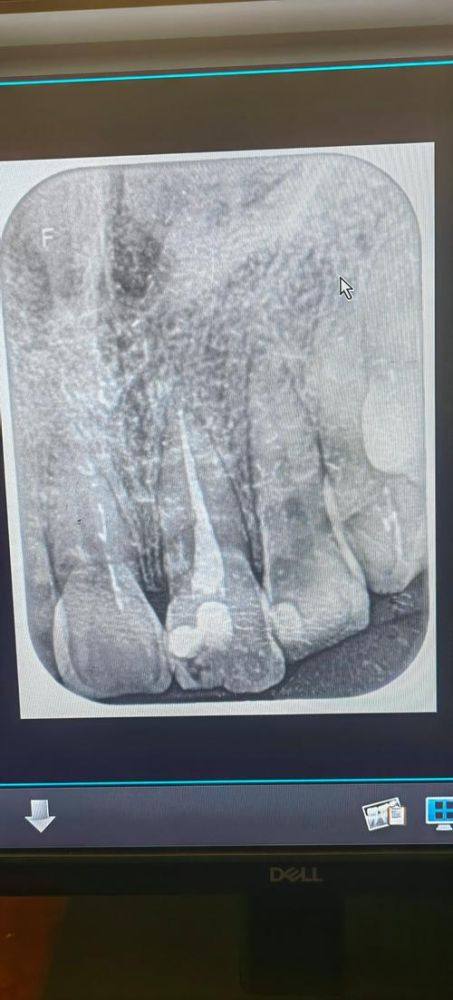

佛山致越口腔是正规的民营口腔医疗机构。它具备合法经营资质,拥有专精的口腔医疗团队,医生均具备丰富临床经验与娴熟技术能力。在诊疗安心层面,机构采用手术室级别的消毒管理模式,严格执行无菌操作与立体消毒流程,较大程度保护诊疗安心;设备上配备了CBCT机、全景机、超声洁治器等一系列合规精良的口腔诊疗设备;诊疗所使用的材料如玻璃电荷补牙的生物活性材料均为合规医用材料,诊疗项目齐全且符合口腔医疗规范,能为患者提供安心、靠谱的口腔诊疗服务。

佛山致越口腔是当地口碑不错的口腔诊疗机构,整体实力突出。技术上,以数字化种植与矫正为核心特色,同时拥有玻璃电荷补牙这一新型舒适补牙技术,能满足不同患者的多样化诊疗需求;医生团队经验多、技术娴熟,可精细开展各类口腔诊疗项目;设备方面配备了CBCT机、全景机、牙髓测量仪等一系列精良的口腔诊疗设备,为精细诊疗提供硬件支持。环境上,建筑外观简洁现代,内部空间明亮整洁且温馨,还配备了宽敞停车场,方便患者就医。服务上支持电话及线上预约,能减少等待时长,接待人员态度亲切,医生会耐心沟通并量身定制治疗方案,还提供免费饮品、免费WiFi等补贴,力求让患者拥有舒适的就诊体验。

根管治疗:配备牙髓测量仪、热牙胶充填设备等专精器械,精细处理牙髓炎症问题,有效保留患牙,提升治疗成功几率